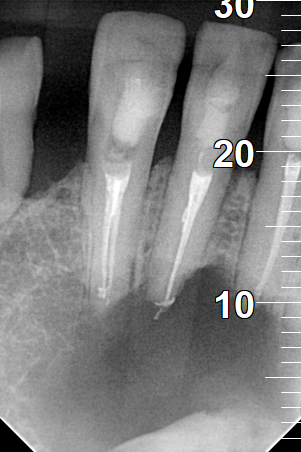

Root canal treatment

BEFORE

AFTER

Clinical photo after the preparation of root canals of the tooth

Clinical photo after the root canal filling